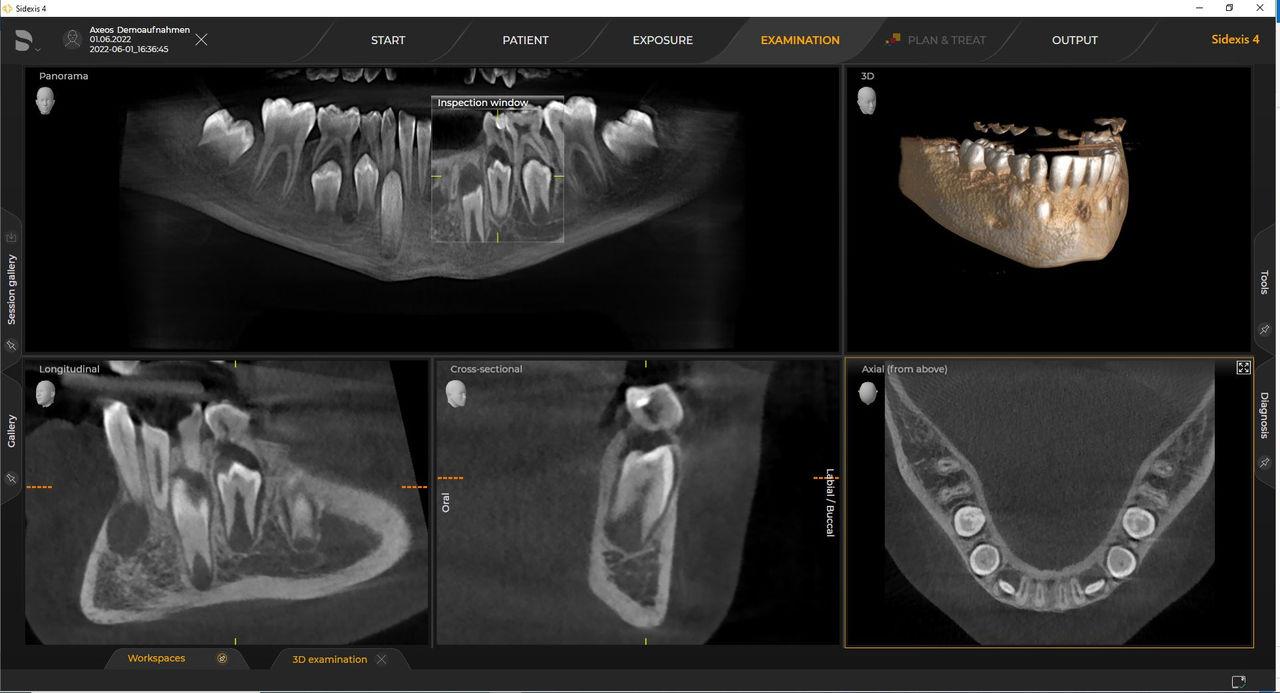

Los numerosos tamaños de volumen garantizan la flexibilidad en la práctica diaria. Examine un área precisa o evalúe la dentición completa, lo que incluye las ATM

Con el modo de dosis baja inteligente, obtiene radiografías 3D en el rango de dosis de una 2D. En el modo HD (hasta 1400), las imágenes individuales se obtienen durante una única rotación y se convierten en un volumen 3D con hasta 80 μm para imágenes de bajo ruido en alta resolución

Las unidades 3D de Dentsply Sirona funcionan exclusivamente con Sidexis 4. Sin embargo, la migración de datos de Sidexis XG a Sidexis 4 es muy fácil. Sidexis 4 permite una experiencia digital completa con las últimas herramientas.